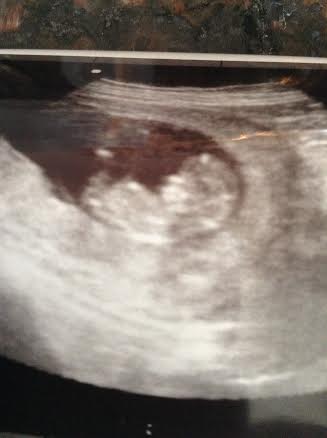

My doctor couldn't find the heartbeat via doppler so I got a surprise 2nd ultrasound at 12 weeks today. Everything looks great and I got a few pictures. Not sure if anything is visible, but I am hoping to get some better shots at my NT scan next week. Thanks for guessing!

Attachment 22506Attachment 22505